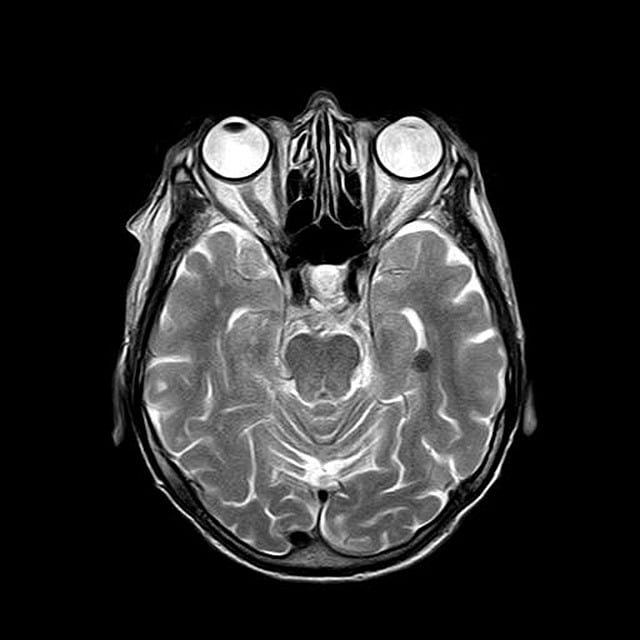

MRI(Magnetic Resonance Imaging)는 인체에 해를 주지 않는 자기장을 활용해 몸 안의 조직과 장기 상태를 정밀하게 찍어내는 검사입니다.

CT나 X-ray와 달리 방사선 노출이 없고, 특히 신경계, 관절, 연부조직, 종양 진단에 강력한 효과를 보입니다.

🧠 [1] 뇌 MRI 건강보험 적용 기준

적용 가능 사례

다음과 같은 경우에는 뇌 MRI에 건강보험이 적용됩니다.

- 뇌졸중 의심(급성 두통, 반신마비, 언어장애 동반)

- 외상 후 출혈 가능성

- 뇌종양 의심(시야장애, 복시, 두통, 구토 동반)

- 뇌염, 뇌수막염 등 감염성 뇌질환 의심

- 신경학적 이상소견이 동반된 간질(경련)

💡 TIP: 단순한 ‘두통’만으로는 보험이 적용되지 않습니다. 반드시 신경학적 이상이 의심되어야 하며, CT 촬영 후에도 추가 진단이 필요하다는 의사 소견이 있어야 합니다.